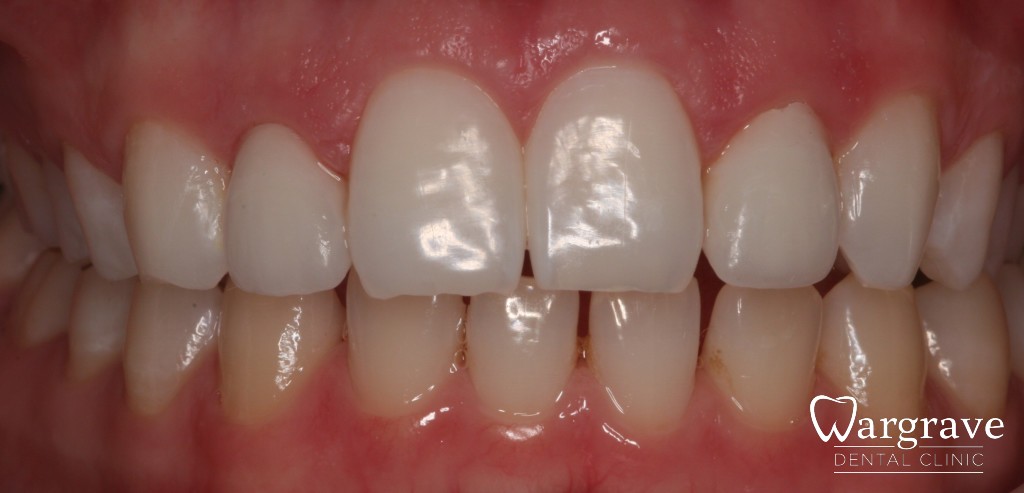

Ceramic crowns

Case 3 – Ceramic crowns at the front of the mouth are highly aesthetic and can blend in with the natural dentition.

before

after